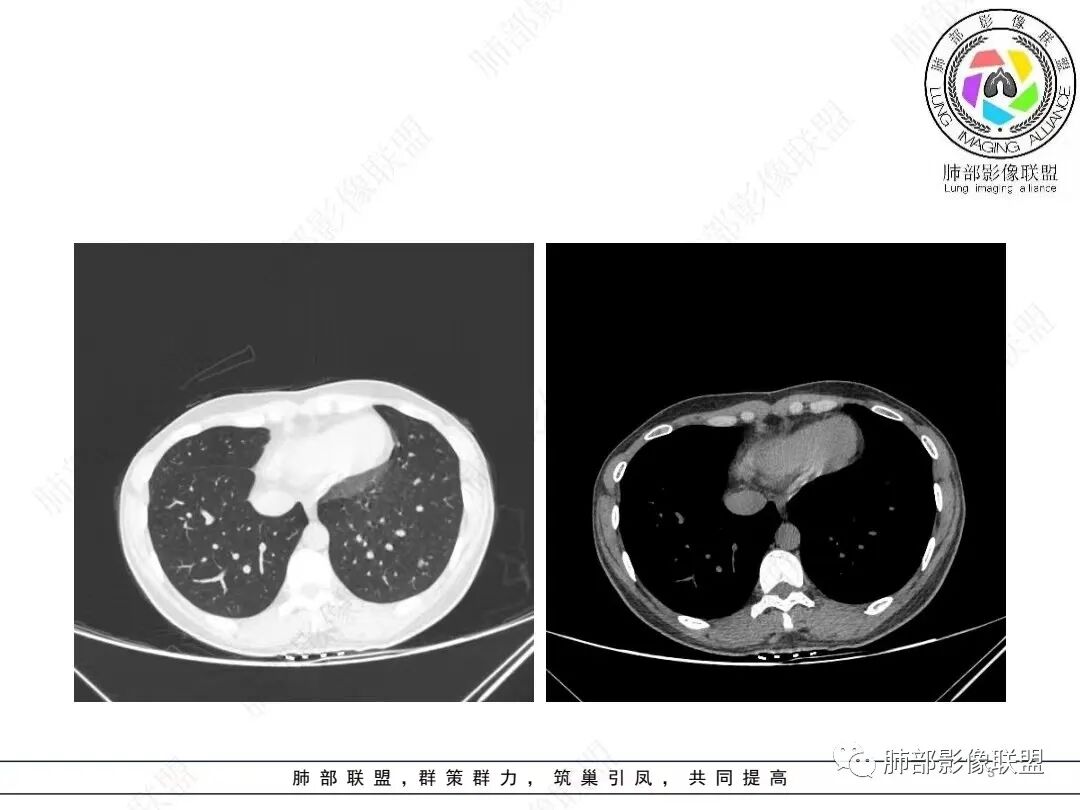

2、影像特点:左肺下叶类圆形结节影,周围可见多发细小毛刺,浅分叶,张力不高,未见胸膜牵拉。病灶内隐约见空泡影(未提供CT值),近端部分血管呈杵状增粗,可疑脐凹征。增强后实性部分有轻度强化。外围病灶,与支气管关系不明确。

4、病例小结:中青年女性偶然发现结节,表面欠光整,内部空泡,不均匀强化,边缘分叶毛刺等都具有影像学上的恶性征象,正如大多数老师所分析与肺腺癌较为符合。部分肺部肿瘤年轻化,尤其是肺腺癌等应当引发我们高度关注。